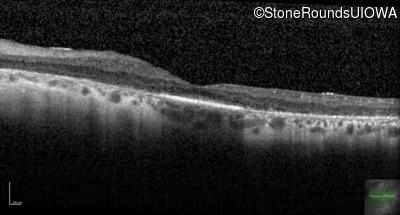

Visit at age: 35 years

Optical Coherence Tomography - Right - 20/100 +1

Exemplar / OCT Stack